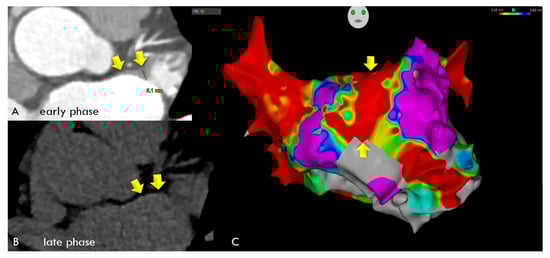

In the comparison of LE-CT with the EA voltage maps, voltage maps were available in a subset of 30 patients. In the per-patient-based analysis, there were 24 agreements (80%) between LE-CT and the voltage maps (21 true positive and 3 true negative) for low-voltage areas (bipolar signals < 0.5 mV). There were six mismatches. In two patients with LE by CT, borderline low-voltage areas were present (0.67 and 0.69 mV); in two patients, LAWT (2.1 mm) was mild; and in two patients, the reasons were unclear (possible artifacts). Agreement was higher, with 28/30 (86.6%) for low-voltage areas <0.7 mV (Figure 5 and Figure 6). Figure 5 shows an example of a 59-year-old-male with paroxysmal AF, left atrial remodeling (LAWT 3.3 mm), and LE with 128 HU on the anterior wall correlating with a low-voltage area on EAM. Figure 6 shows a case with linear LE indicating diffuse fibrosis, with LVA and recurrent AFIB after ablation.

Figure 5. A 59-year-old-male with paroxysmal AF, a BMI of 21.5, the CVRF of dyslipidemia, and left atrial wall thickness (LAWT) of 3.3 mm, with a low-voltage area on EAM (anterior LA wall, green/yellow area) (upper panel, (A)) matching with focal LE (128 HU) on late enhancement (LE) CT (lower panel, (B)).

Figure 6. A 59-year-old male with a BMI of 27.8 kg/m2, and a LVEF of 68% with paroxysmal AFIB and severe left atrial wall thickening (LAWT) with a maximum of 5.1 mm during early-phase CT (Panel (A), arrows) and linear late enhancement during late-phase CT (Panel (B), arrows), indicating diffuse fibrosis, which was correlated with low-voltage areas along the entire anterior left atrial wall during electroanatomical mapping (EAM). (Panel (C)) All 20 spots were positive for low-voltage areas of <0.5 mV, shown as red areas (yellow arrows), with values ranging from 0.015 to 0.12 (mean: 0.024 mV). While LA ablation with pulmonary vein isolation was successful, the patient experienced recurrent AFIB after 3 months, and a second LA ablation was performed 7 months later.